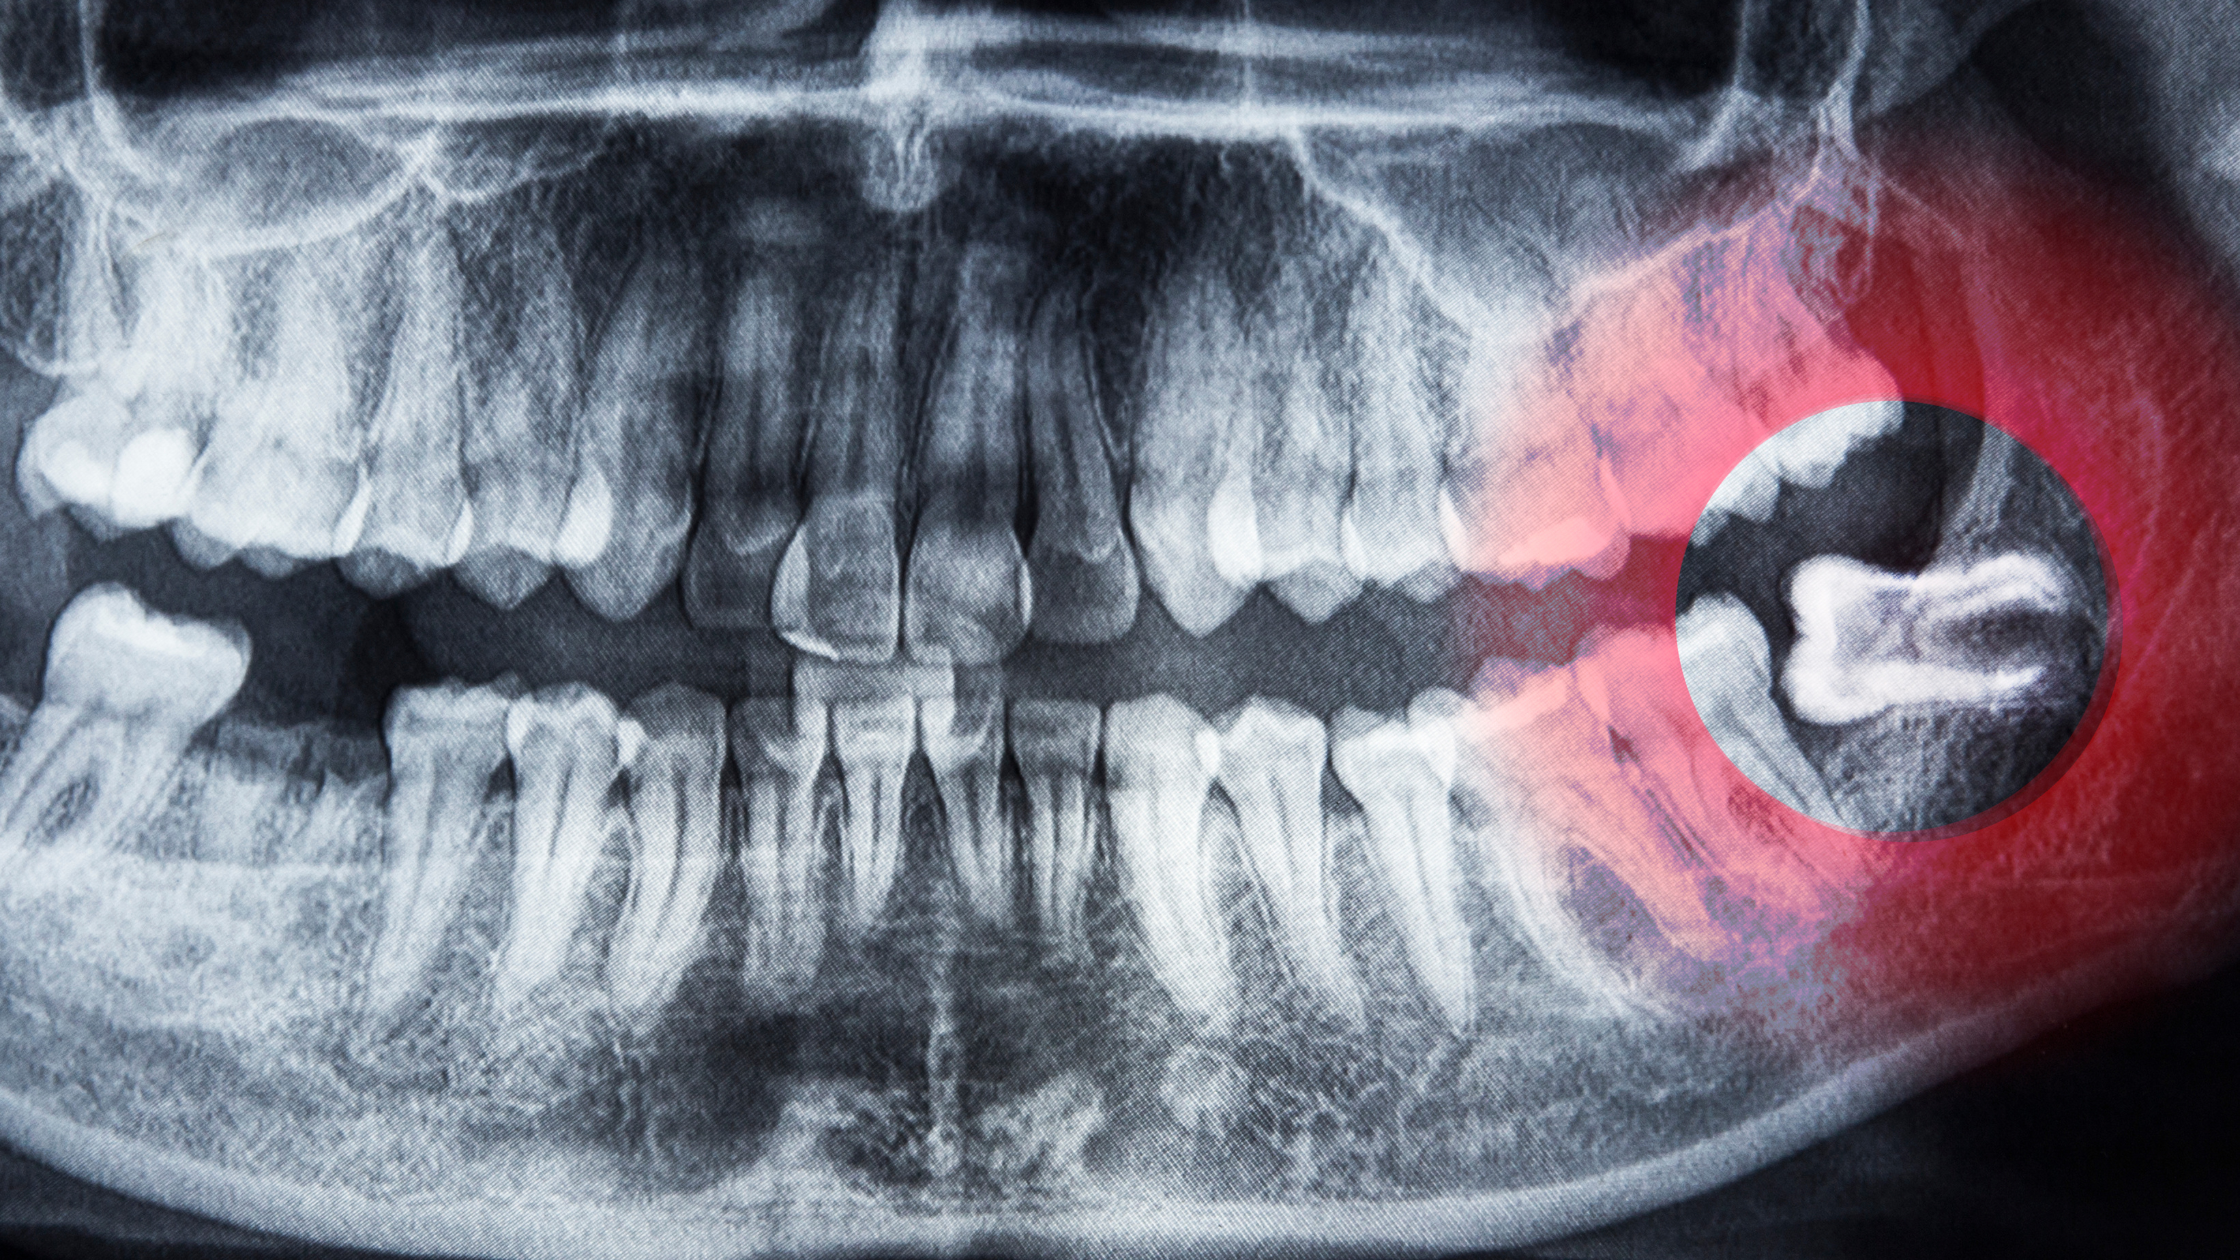

Adiar o tratamento saúde bucal é um erro comum que pode trazer consequências graves. Muitos acreditam que pequenos desconfortos dentários se resolvem sozinhos, mas a realidade é outra: o atraso no cuidado pode transformar problemas simples em situações complexas e dolorosas. O que acontece quando você adia o tratamento odontológico? Quando um pequeno desconforto não …